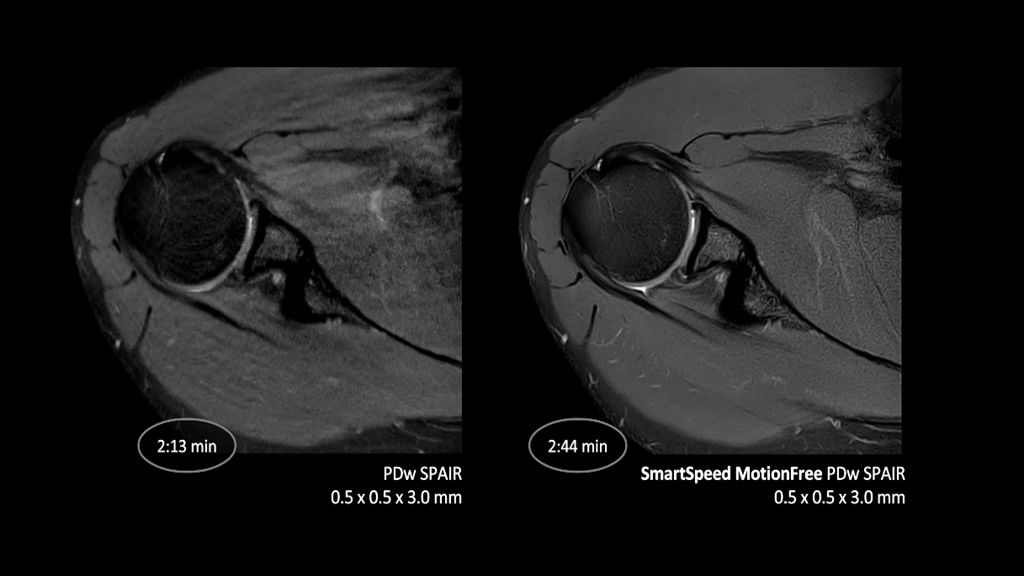

2. Reconstruction technology Compared to conventional (SENSE/ Compressed SENSE, SmartSpeed AI) imaging. Sharpness was evaluated with phantom scanning.